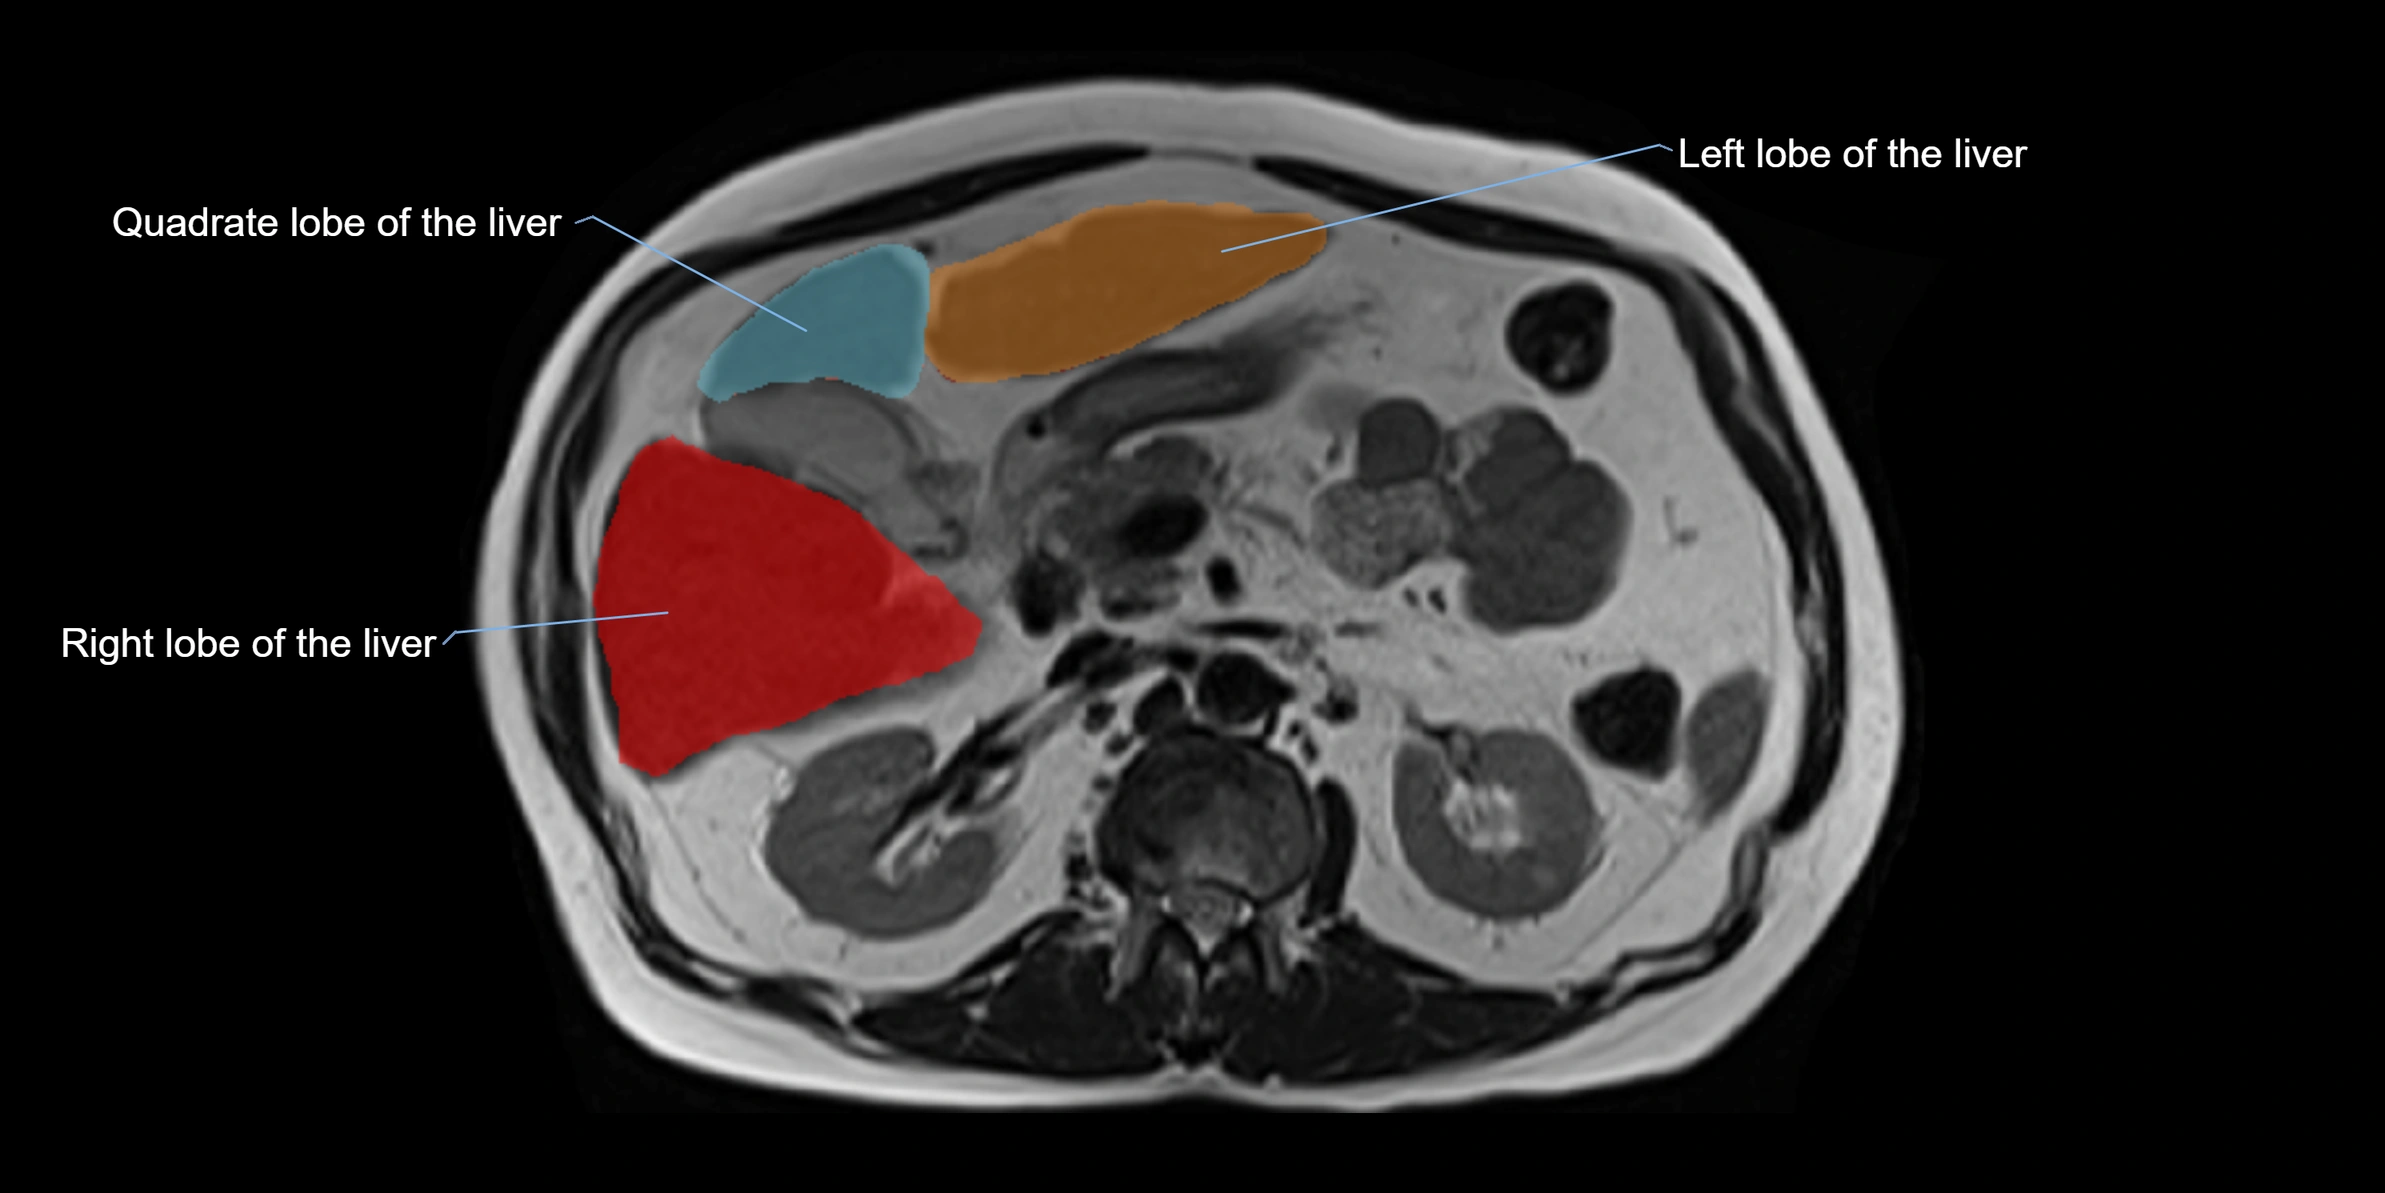

The caudate lobe of the liver is a distinct anatomical subdivision of the liver, designated as segment I in Couinaud’s classification. It lies on the posterior surface of the liver, between the fissure for the ligamentum venosum (left boundary) and the groove for the inferior vena cava (IVC) (right boundary). Superiorly, it is related to the posterior liver surface, and inferiorly it is separated from the left lobe by the porta hepatis.